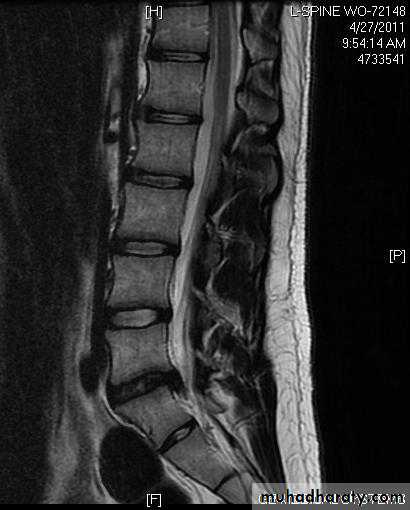

X-rays: show an abnormal narrowed disc space and to exclude bone diseases. After several attacks the disc space may be narrowed and small osteophytes appear.CT and MRI are more reliable than myelography.

CHRONIC INTERVERTEBRAL DISC DEGENERATIONMRI:

Bulging of the annulus fibrosus in both sagittal and axial projections and diminished thickness and reduced signal intensity (dehydration) of the degenerating disc.

Imaging:X-rays will show features of disc degeneration or spondylolisthesis. Measurement of the spinal canal can be carried out on CT and MRI.